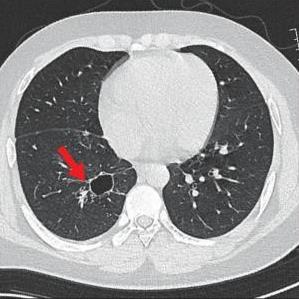

• 侵袭性肺真菌病的支气管镜表现及介入治疗效果

2025, 31(9):81-90. DOI: 10.12235/E20250317

摘要 (112) HTML (56) PDF 6.06 M (77) 评论 (0) 收藏

摘要:目的 探讨侵袭性肺真菌病(IPFD)的支气管镜表现,并评估介入治疗的安全性和疗效。方法 回顾性分析2018年5月12日-2025年5月12日于该院行支气管镜检查的35例IPFD患者的临床资料,观察IPFD的支气管镜表现及介入治疗效果。结果 共收集35例患者临床资料。其中,男22例,女13例,患者年龄(53±14)岁。基础疾病包括:血液系统恶性肿瘤10例,长期应用糖皮质激素者5例,2型糖尿病者4例,肺部恶性肿瘤2例,器官移植1例。胸部CT显示:肺部病变累及单肺叶者19例,累及多肺叶者16例。支气管镜下表现主要为:黏膜充血水肿29例(82.9%)、坏死物堵塞管腔22例(62.9%)、大量黏稠脓性分泌物17例(48.6%)、支气管部分狭窄或闭塞16例(45.7%)、黏膜坏死9例(25.7%)、黏膜出血5例(14.3%)、真菌球3例(8.6%)。其中,32例(91.4%)接受全身性抗真菌治疗,17例(48.6%)接受支气管镜局部两性霉素B灌注治疗,10例(28.6%)采用活检钳钳除病灶,6例(17.1%)采用冷冻探头冻取病灶,4例(11.4%)接受氩气刀治疗。28例(80.0%)临床症状明显改善,肺部影像学病灶缩小或消退;4例(11.4%)病灶稳定;3例(8.6%)未完成治疗。结论 IPFD多见于免疫抑制宿主,支气管镜常表现为:坏死物堵塞管腔、伴脓性分泌物、支气管管腔狭窄和局部黏膜充血水肿或坏死。全身抗真菌药物联合支气管镜下介入治疗,安全性高,且疗效好。